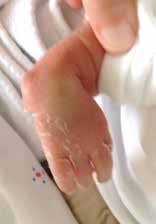

Aus handchirurgischer Sicht muss schließlich geprüft werden, ob eine Operation indiziert ist. Dazu muss die Gesamtsituation betrachtet werden. Sind z. B. weitere Fehlbildungen an anderen Gliedmaßen oder Organen vorhanden? Wie dringlich ist die Versorgung der anderen Fehlbildungen? Vorrangig ist stets die Behandlung lebenswichtiger Organe wie z. B. des Herzens oder der Speiseröhre durch die entsprechenden Fachdisziplinen. Weiterhin wird geprüft, ob eine Mitarbeit des Kindes während der postoperativen Nachbehandlung erforderlich ist. Diese ist gegebenenfalls erst zu einem späteren Zeitpunkt motorisch und von seiner geistigen Entwicklung her möglich. Sind Eingriffe am Skelettsystem erforderlich, sollten diese keine Wachstumsstörungen hervorrufen. Der natürliche Verlauf mit möglicher Adaptation sollte immer gegenüber einer operativen Behandlung abgewogen werden, denn Kinder lernen in der Regel spontan ihre Finger‑, Hand- und Armdeformität funktionell einzusetzen. Betroffene Patienten entwickeln häufig eine große Geschicklichkeit trotz vorhandener Fehlstellung (Abb. 1). Für eine ästhetische Korrektur darf keine Funktion verschlechtert werden 4.

Am Ellenbogen wird die aktive und passive Beuge- und Streckfähigkeit beurteilt und die Unterarm-Umwendung im proximalen Radio-Ulnargelenk geprüft. Bei einer Ellenbogenaplasie kann die Bewegung am Ellenbogen aufgehoben, aber ein vollständiger Faustschluss möglich sein (Abb. 2a–c). Die Greiffunktion bei einer Symbrachydaktylie vom Spalthand-Typ kann auch mit zwei aktiv beweglichen Fingern, die aufeinander ausgerichtet sind, für einen 2‑Punkt-Griff sehr gut geeignet sein (Abb. 3a u. b). Bei einer Peromelie (Abb. 4) kann eine Transplantation von zwei Zehen zur Schaffung eines Spitzgriffs 8 führen. Wird dies nicht gewünscht, kann eine (myoelektrische) Prothesenversorgung mit den Eltern besprochen werden. Ein Therapieziel kann die Schaffung einer fünfstrahligen Hand sein, z. B. bei numerischen Fehlbildungen wie einer Hexadaktylie (Abb. 5) oder einer Doppeldaumen-Anlage. Ein weiteres wichtiges Therapieziel ist die Schmerzreduktion. Bei einem Schnürfurchen-Syndrom können im Wachstum Schmerzen auftreten; es besteht die Gefahr einer knöchernen Durchspießung (Abb. 6).